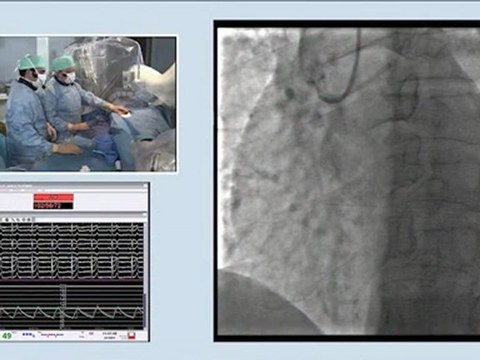

01 recanalization of right in-stent iliac occlusion. thrombo-atherectomy by rotarex - incathlab.com